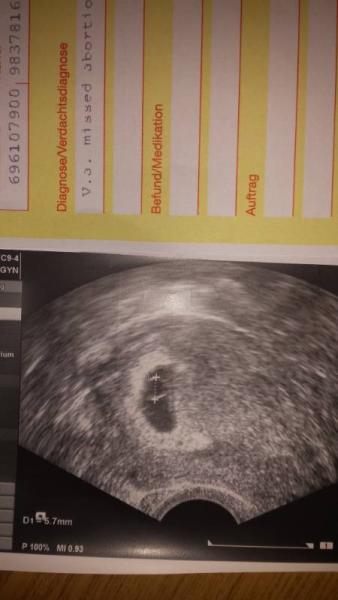

Komm grad vom Fa. Dottersack ist gut gewachsen nur immer noch kein Embryo zu sehen. Hab Überweisung ins kh zur Ausschabung bekommen.

Was meinst du mit Alternative zur Ausschabung? Wenn ich das Bild näher betrachte ist doch rechts neben dem dottersack ein Körper zu erkennen oder nicht????

Ich bin nur ehrlich, dass ich denke, dass es nicht gut aussieht, weil der Embryo zu dem Zeitpunkt schon größer ist als der Dottersack. Da sieht man ihn eig sehr gut.

In der Überweisung steht Missed abortion....

Ich sehe auf deinem Bild ehrlich gesagt nur den Dottersack. Und der Embryo ist wirklich in dieser Woche schon relativ groß gegenüber dem Dottersack. Ich kann dir bis jetzt nur Vergleichsbilder von meiner letzten Schwangerschaft zeigen. Da siehst du wie es in der Woche eig aussieht. Natürlich drücke ich dir trotzdem die Daumen, dass alles gut ausgeht!!! Versteh mich bitte nicht falsch. Ich wünsche dir natürlich nur das Beste!!! Bild links bei 7+4 Bild rechts bei 8+6